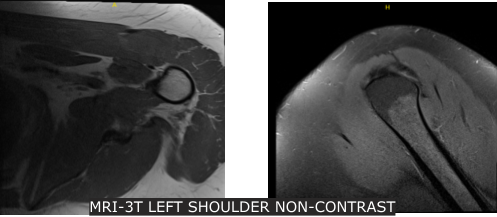

Xray were reviewed and discussed that his left shoulder showed normal radiographs. Advised patient to take MRI for us to see the reason behind and found out partial thickness tear of the subscapularis tendon though there is no high-grade partial or full thickness rotator cuff tear. Presence of supraspinatus and infraspinatus tendinosis.